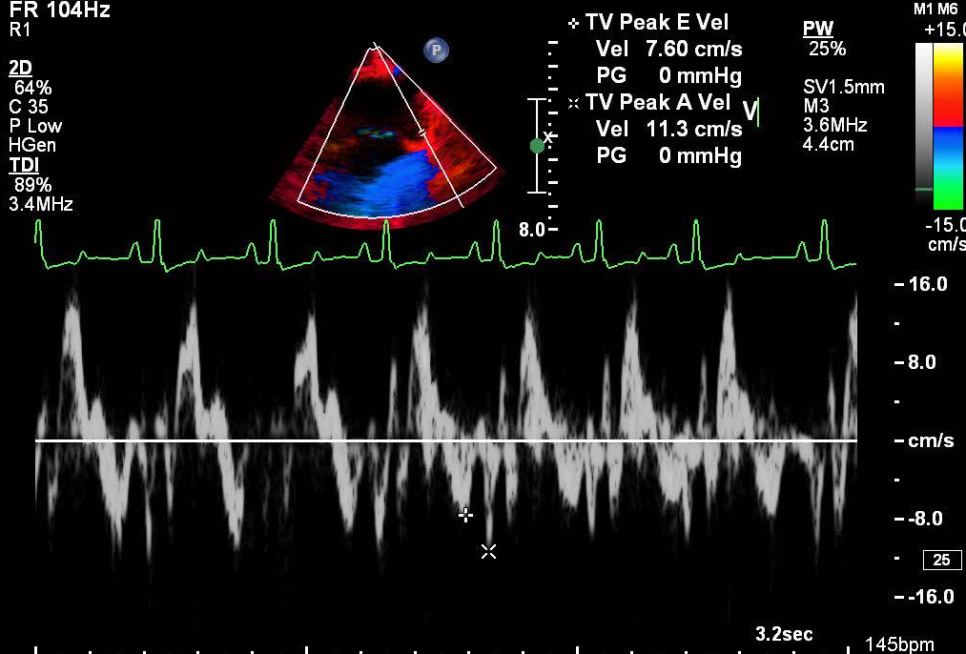

심장 질환 진단에서 가장 중요한 것은 ‘심장의 상태를 얼마나 정확하게 볼 수 있느냐’입니다. 저희 센터는 대학병원급 하이앤드 초음파 장비를 도입하여, 실시간 3D 렌더링으로 정밀 진단이 가능하며, 심장의 구조·혈류·기능을 실시간 고해상도로 관찰합니다.

미세한 판막 움직임, 혈류 속도 변화, 심방·심실 크기와 수축력까지 정밀하게 분석할 수 있어, 심장질환의 조기 발견과 치료 계획 수립에 큰 차이를 만듭니다.